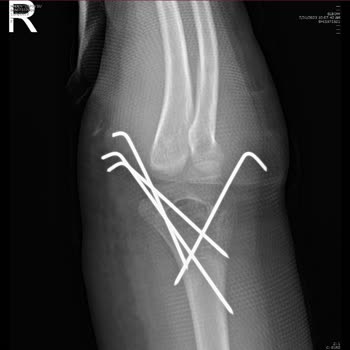

Zeytinburnu'daki Koç Üniversitesi acil bölümüne 03.10.2024 tarihinde kızım z. D**. Ş. Sol ayak bileğinde bileğinde şiddetli ağrıyla acil bölümüne götürdüm. Acilde röntgen çekildi. Sol ayağında olmasına rağmen 2 ayağını da röntgen çekilmiş olduğunu gördük. Acil de ayağında kırık olmadığı ortopedi dok...